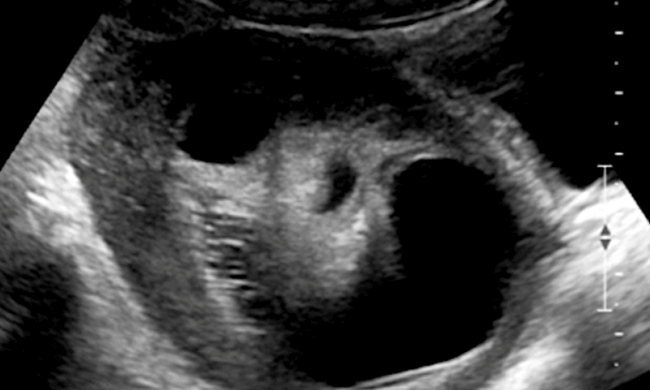

"Water Cysts" or Functional ovarian cysts are the most common cysts in the reproductive age. Functional cysts are the result of normal ovulation function. They contain only fluid and usually resolve in a month or two, hence treatment is rarely needed. They are usually less than 5cm although sometimes they can be as large as 8cm.